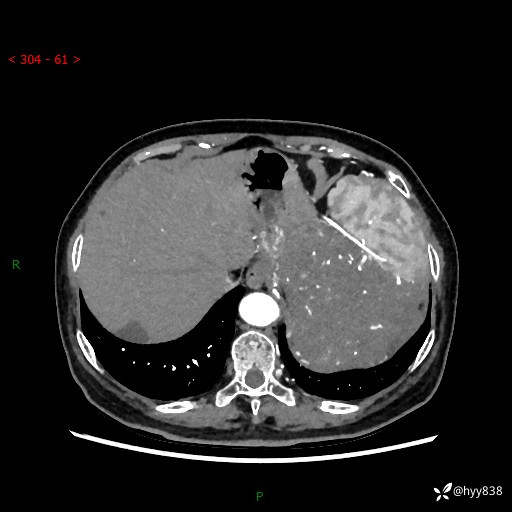

据说只有腹膜后,才能见到如此巨大的肿块---(有结果)

主诉:发现腹膜后占位1周

简要病史:患者1周前因头晕在当地第二人民医院检查发现左侧腹膜后区巨大富血供占位性病变,患者自诉腹部稍硬,无其他不适,无血尿,无腰痛等不适,患者为求进一步治疗来我院,门诊以“腹膜后占位性病变”收入我科。 起病以来,患者精神、饮食、睡眠可,大便正常,小便如上述,体力体重无明显改变。

临床诊断:腹膜后占位

腹部CT增强(动脉期+静脉期 ) ---平扫外院